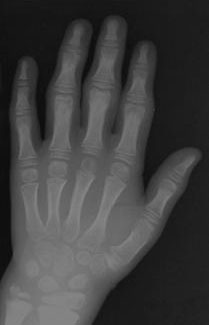

Exostoses apenas poupam crânio e face Exostose Múltipla (EM) também chamada de Osteocondromatose Hereditária Múltipla é uma condição relativamente rara, com cerca de um afetado

Diagnóstico tardio marca desordem rara Conhecido por uma variedade de nomes (Displasia Progressiva Pseudo Reumatóide Juvenil), esta é uma desordem rara, estimada por afetar cerca

Tronco curto e braços longos são típicos Displasia Espondilo Epifisária é uma designação de diagnóstico não específica que simplesmente descreve as manifestações primárias radiológicas como